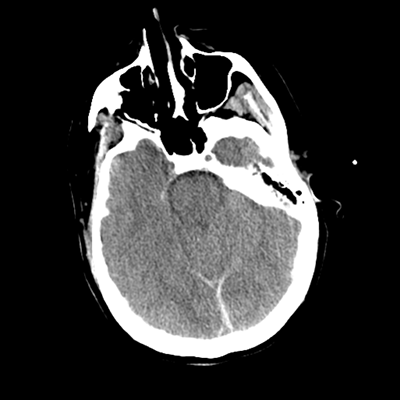

The patient goes down to CT. The following images are obtained. The subdural fluid collection is stable, as is the ventricular caliber.

Starting with the non-contrast head CT, we can appreciate that there's actually not much residual subarachnoid blood at all; it's essentially all resorbed already (and cleared through the EVD). The ventricular caliber is stable. With the CTA head (for convenience's sake, the MIPs were shown), it's subtle, but we can see that the PCAs on each side are not as smooth and regular. The right MCA, starting at the bifurcation, also becomes narrower. This is [radiographic] vasospasm. Now, looking at the CT perfusion-- specifically, the Tmax (MTT) map that were selected-- there's clearly some abnormality within the bilateral cerebellar hemispheres and occipital lobes. Not a lot, but it's there. Delving further into this map, we can appreciate that the areas of abnormality are mainly green, signifying that these areas have Tmax > 6 seconds. This is the threshold that is specific, not sensitive, for vasospasm.

Putting this all together, we have thus identified radiographic vasospasm with the vessel imaging, with perfusion abnormalities that are concordant with it. Does the area of vasospasm and hypoperfusion correlate with the patient's clinical exam?

Yes! It does. The patient had a decline in level of consciousness with diffuse loss of motor function. This does correlate to the basilar territory. (Alternatively, bilateral MCA vasospasm could also be responsible, reminding us that a decline in consciousness could technically be focal/multifocal.) Thus, we can say that this patient does have clinical vasospasm. Whether this will develop into irreversible DCI remains to be seen; at least, the non-contrast head CT and the other portions of the CT perfusion (not shown) currently don't [yet] suggest infarction.